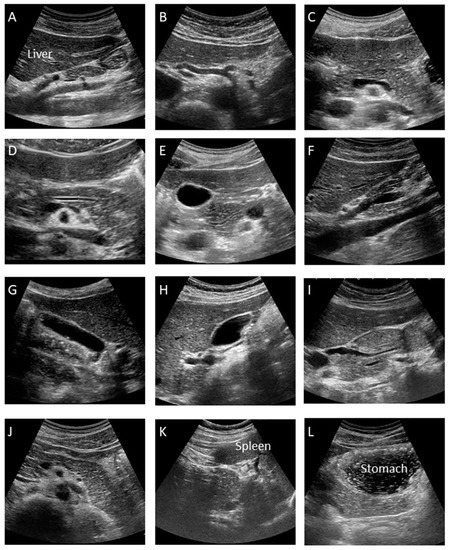

This is the manual for the examination of the pUS. At our institution, at least twelve pictures are taken according to the manual as shown Figure 2, which may minimize operator variability.

A. Median Longitudinal Scan: Visualize the celiac artery (CA) and superior mesenteric artery (SMA) longitudinally and check for lymph node swelling or main pancreatic duct dilation.

B. Transverse Scan: Rotate the probe into the transverse direction and visualize the aorta (Ao), celiac artery (CA), splenic artery (SpA) and common hepatic artery (CHA).

C. Transverse Scan: Check the splenic vein (SpV) and dorsal pancreas by visualizing the pancreatic body transversely as much as possible.

D. Transverse Scan: Enlarge the image and check the presence of main pancreatic duct (MPD) dilation by measuring its diameter at the pancreatic body. It appears as a thin hypoechoic line bordered by two echogenic margins. The upper limit of the main duct is 2.5 mm at the body.

E. Transverse Scan: Observe the pancreatic head by shifting the probe toward the right side of the patient. Follow the MPD from the pancreatic body to the ampulla as much as possible and measure the duct size of the MPD at the head.

F. Right Subcostal Longitudinal Scan: Rotate the probe toward the longitudinal position and observe the lower part of the pancreatic head and uncinate as well as the portal vein and inferior vena cava (IVC).

G. Right Subcostal Margin Scan: Detect the gallbladder longitudinally and check the size of the gallbladder and the existence of abnormalities, such as stones or debris by moving the patient into the left lateral decubitus position.

H. Right Subcostal Longitudinal Scan: Observe the hilar hepatic area, portal vein, common bile duct, and superior aspect of the pancreatic head. Check for bile duct dilation by moving the patient into the left lateral decubitus position.

I. Right Subcostal Longitudinal Scan: Observe the pancreatic head and check for MPD narrowing or common bile duct (CBD) stricture by following the bile duct, which is done by moving the patient into the left lateral decubitus position.

J. Left Subcostal Longitudinal-Oblique Scan: Visualize the pancreatic body to tail in the longitudinal plane by shifting the probe from the pancreatic body to tail, along the splenic vein.

K. Left Intercostal Scan: View the pancreatic tail by detecting the splenic hilar, located at the dorsal side of the splenic vein, by moving the patient into the right lateral decubitus position.

L. Left Subcostal Tilting Scan and The Liquid-Filled Stomach Method: Screen the pancreatic body to tail thoroughly using the liquid-filled stomach method. The pancreatic body to tail can be visualized more clearly by moving the patient into the right lateral decubitus position.

Figure 2. Standard recording sites during special pancreatic US (12 images). (A) Median Longitudinal Scan. (B) Transverse Scan. (C) Transverse Scan. (D) Transverse Scan. (E) Transverse Scan. (F) Right Subcostal Longitudinal Scan. (G) Right Subcostal Margin Scan. (H) Right Subcostal Longitudinal Scan. (I) Right Subcostal Longitudinal Scan. (J) Left Subcostal Longitudinal-Oblique Scan. (K) Left Intercostal Scan. (L) Left Subcostal Tilting Scan and The Liquid-Filled Stomach Method.